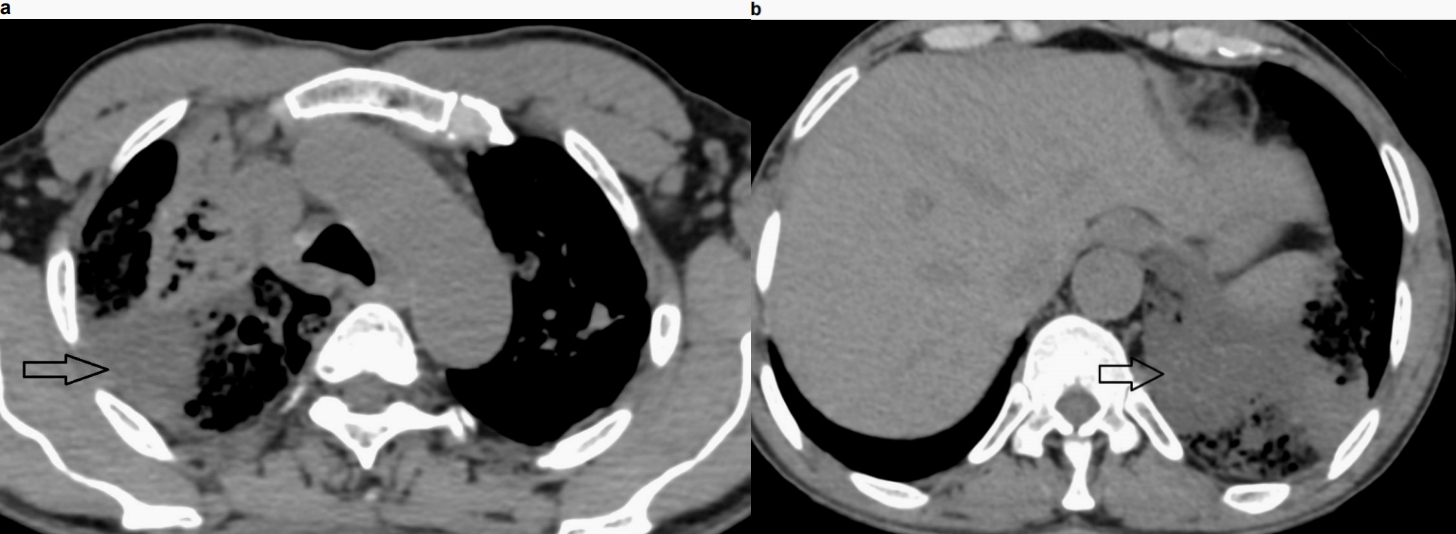

显示双肺广泛实变,其间有磨玻璃影、间隔增厚及多发小囊性/空洞区。部分实变显示内部低密度区(衰减值范围为15-25 HU)。无胸腔积液

或明显的纵隔淋巴结肿大。

图3 胸部非增强CT,纵隔窗,轴位图像示右上叶(3a)和左肺底(3b)实变区内的低密度区(黑色箭头)。